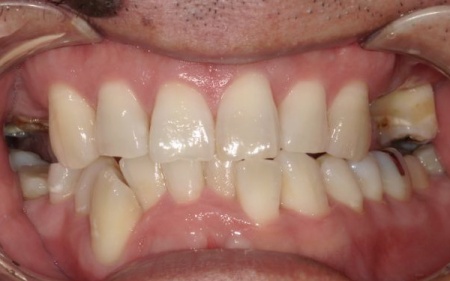

最後に、痛みや違和感がないか、見た目や噛み合わせに問題がないかを確認し、治療を終了しました。

患者様は「可能な限り自分の歯を残したい」と希望されており、長期的な安定と清掃のしやすさを考慮して、②のインプラントブリッジによる治療を選択されました。

インプラントがしっかりと骨に定着したことを確認したら、精密な型取りを行い、ブリッジを作製して装着しました。

インプラント治療と併せて保存可能な歯の治療も進め、右上の一番奥の歯と右下の奥歯(前から5番目と6番目)に対して、細菌感染した神経を取り除いてから薬を詰める根管治療を行い、CAD/CAM冠という白い被せ物で修復しました。

さらに、上前歯(右上の犬歯から左上の犬歯まで)、右下の4番目の歯に対しては、虫歯治療を行っています。